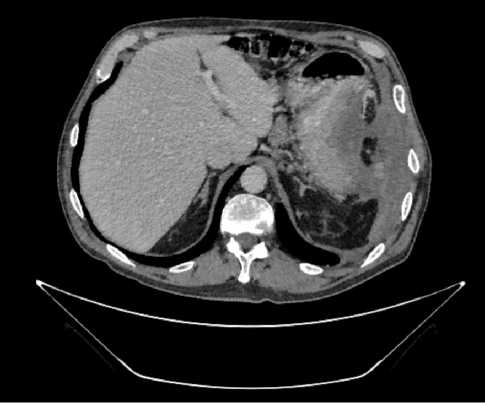

Выполнена компьютерная томография (КТ) органов грудной клетки, брюшной полости в июле 2019 г. Инфильтративных изменений в легких не обнаружено. Выявлено новообразование антрального отдела, малой кривизны и передней стенки желудка, распространяющееся на заднюю стенку, преимущественно на препилорический отдел. Имелись признаки локального перехода образования на большой сальник, гепатодуоденальную связку с периваскулярным ростом и признаками лимфоваскулярной инвазии. Многочисленные забрюшинные ЛУ сливались между собой в конгломераты размерами до 40 × 29 мм с частичным вовлечением почечных артерий. Также билобарно обнаружены немногочисленные очаговые образования в печени до 10 мм. Высказано подозрение на перитонеальный канцероматоз (рис. 3).

Рис. 3. Результаты компьютерной томографии органов брюшной полости у пациента 80 лет с диагнозом метастатический рак желудка с признаками микросателлитной нестабильности (июль 2019 г., до лечения)

Fig. 3. Results of a CT scan of the abdomen in an 80-year-old patient with metastatic MSI-H gastric cancer (July 2019, before treatment)

В результате обследования был установлен диагноз рака антрального отдела желудка (c)T4аN3вM1. По решению онкологического консилиума, учитывающего молекулярно-генетический профиль опухоли, а также возраст пациента, выраженность сопутствующей патологии (в анамнезе острое нарушение мозгового кровообращения (ОНМК), острый инфаркт миокарда (ОИМ), фибрилляция предсердий (ФП), постоянная форма), ограничивающей проведение ПХТ, была начата ИТ 1 линии пембролизумабом. С сентября 2019 г. по декабрь 2021 г. проведено 29 циклов ИТ 1 линии по схеме пембролизумаб в монорежиме с максимальным эффектом частичный регресс (рис. 4). Осложнений лечения не зарегистрировано.